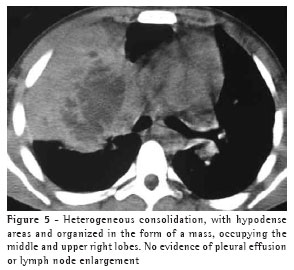

The most frequent finding in the imaging, present in the seven patients, was ill-defined consolidation (Figures 1, 2, 3 and 4). Five of patients presented air bronchogram, principally at the periphery of the lesion. In three cases, the consolidation was organized in the form of a mass. In six of the seven patients, irregular areas of cavitation were observed within the consolidations. Multiple cavitations were seen in five patients, and a singular cavitation was observed in one patient. In the patient presenting no cavitation, there were hypodense areas suggestive of necrosis (Figure 5). Only one of the patients presented air-fluid levels within the cavities.

Cavitated lesions predominated in the upper lobes, four in the right lobe and one in the left lobe. In one patient, the middle lobe was also affected. In two cases, such lesions occurred in the lower lobes, one in the right lobe and one in the left lobe. In four cases, the lesions affected only the lobes mentioned above and were therefore unilateral. In the remaining three cases, the contralateral lung was also affected, albeit to a lesser degree. In one case, there was also relatively thin-walled, multiloculated cavitation, without an air-fluid level, in the middle lobe.

None of the other findings described in the literature (pulmonary coin lesion, pleural effusion, pneumothorax, lymph node enlargement and soft tissue involvement) were observed in any of the patients.